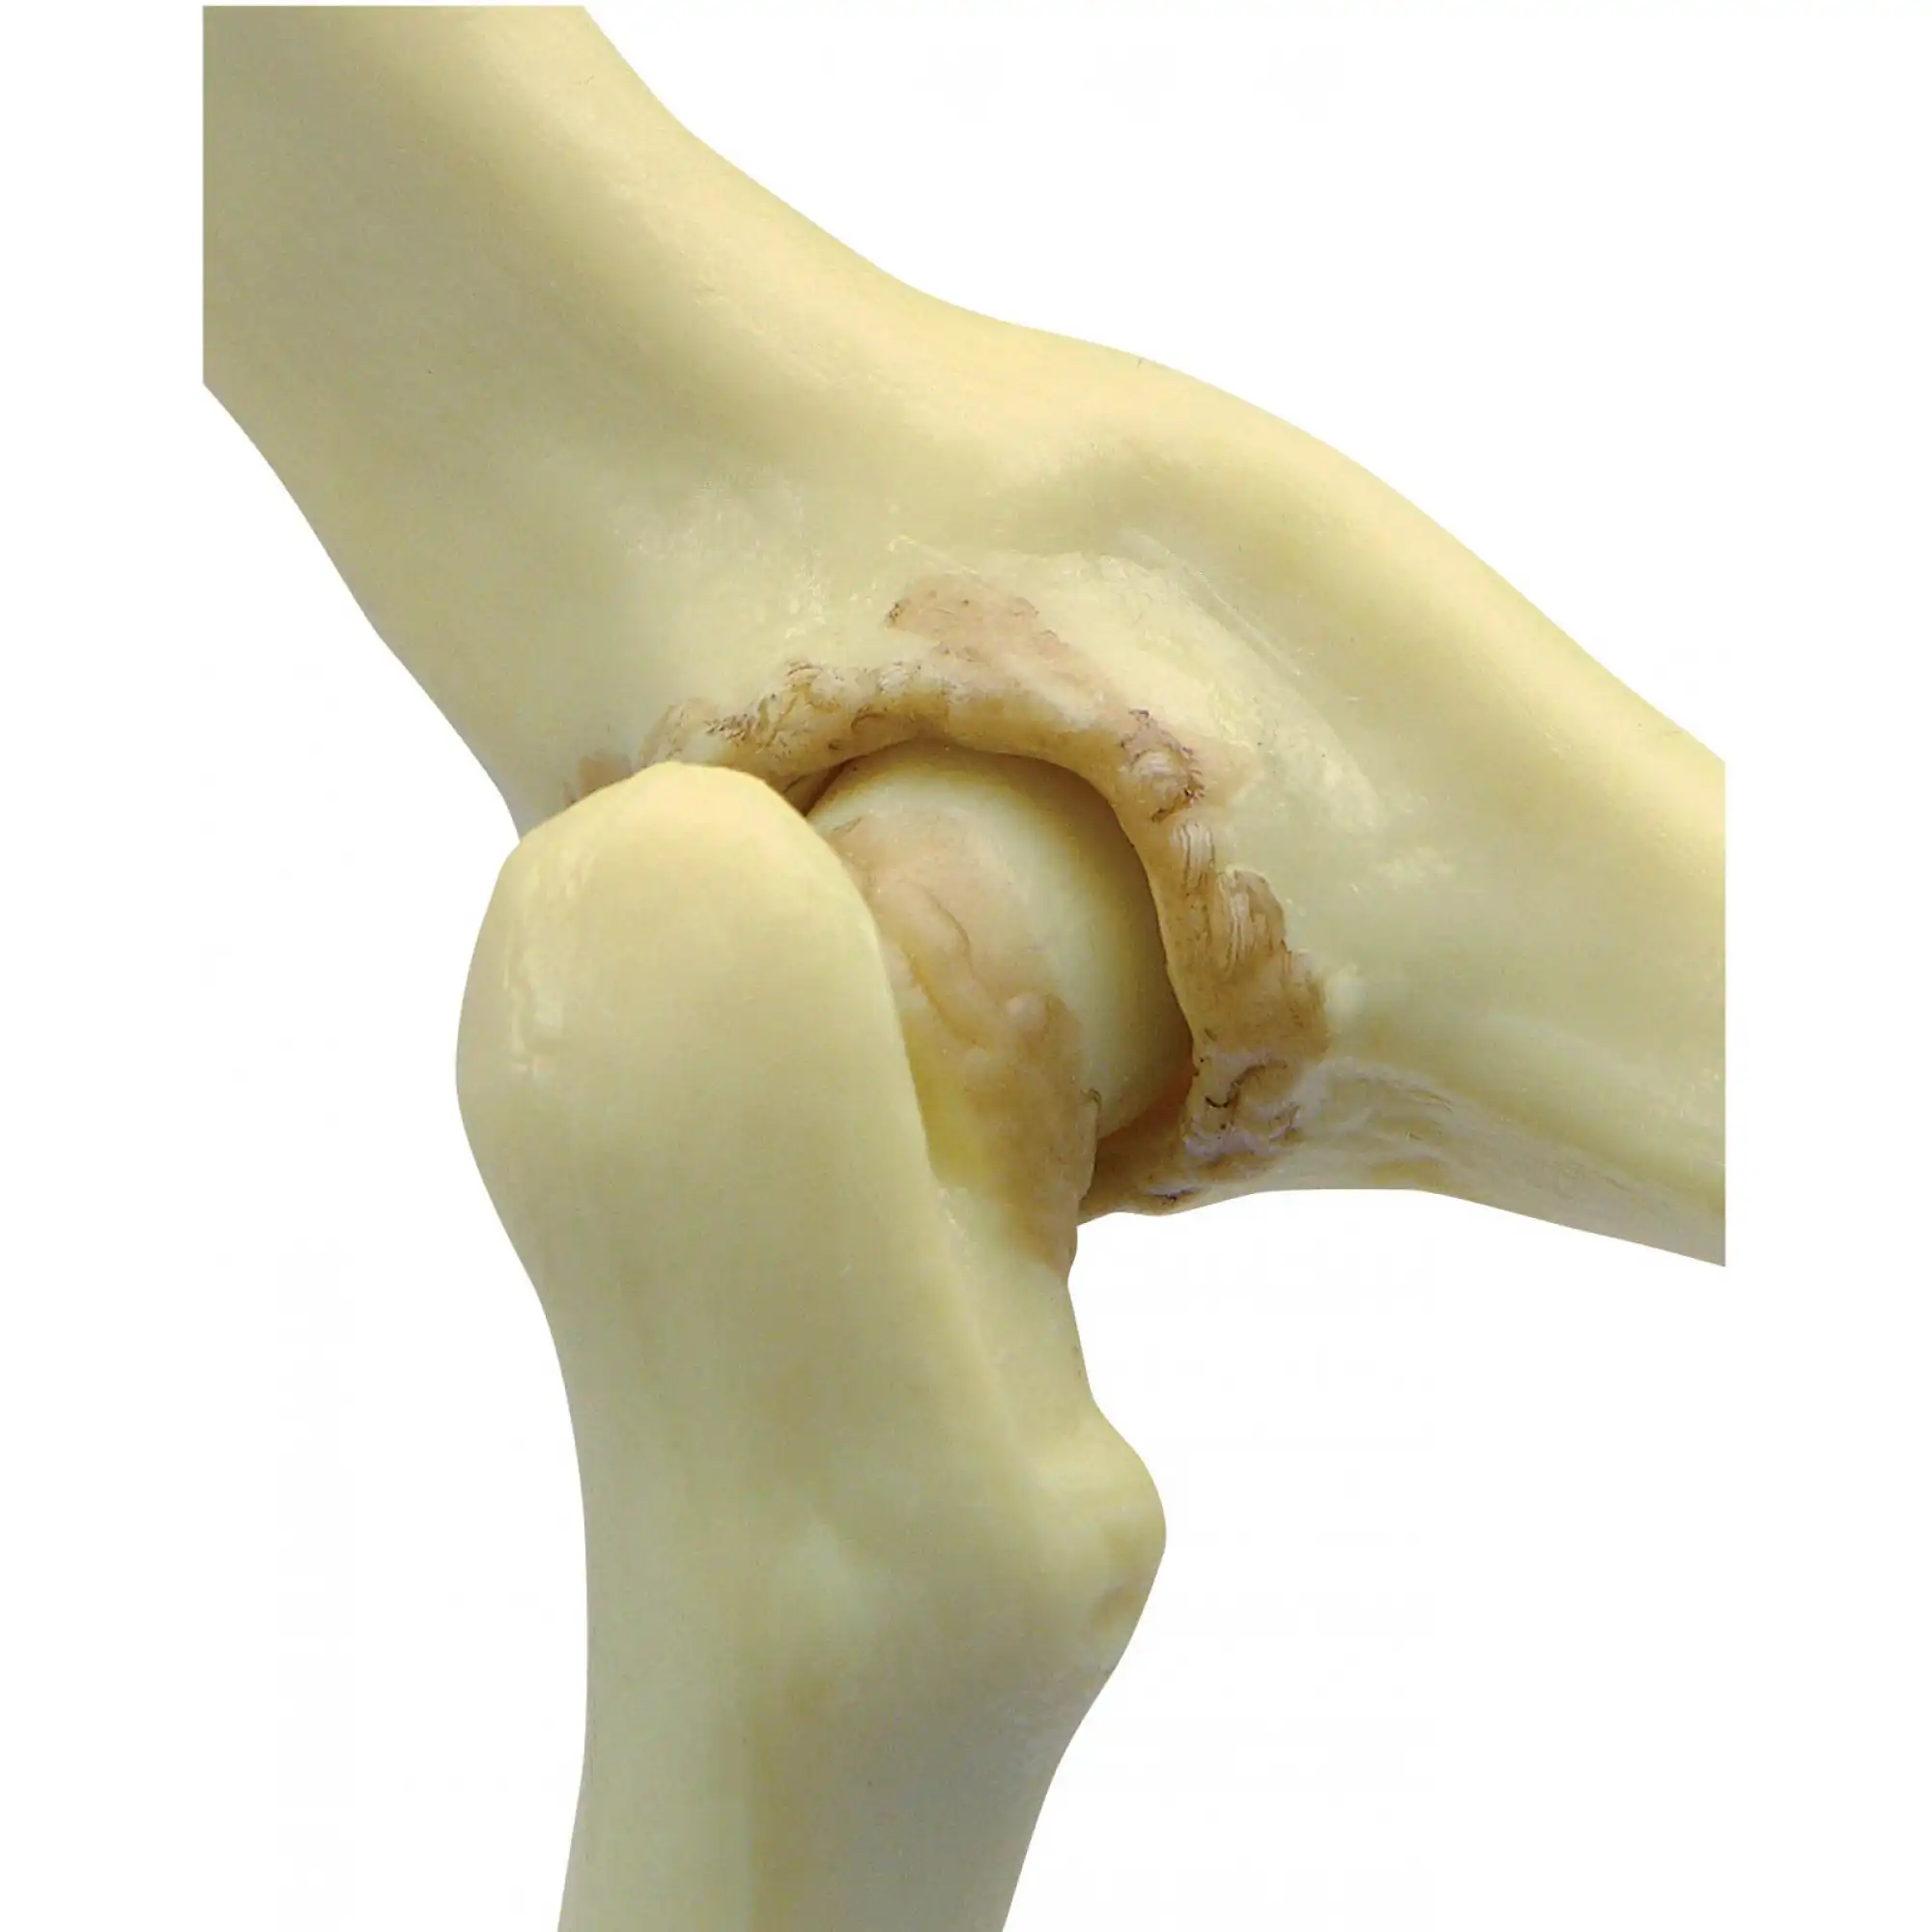

استئوفیت و خار استخوانی چیست؟نام دیگر این بیماری خار استخوانی است، این زائده کوچک و به ظاهر بیخطر، میتواند منشأ دردهای طاقتفرسا و محدودیتهای حرکتی آزاردهنده باشد. اما آیا واقعاً همه چیز در مورد این عارضه را میدانیم؟ آیا پزشکان از تمام زوایای پنهان آن آگاهند؟

علت استئوفیت زانو

استئوفیت می تواند ناشی از عوامل مختلفی باشد، اما شایع ترین علت آن آرتروز زانو است. آرتروز، تخریب تدریجی غضروف مفصلی است که منجر به ساییدگی استخوان ها روی هم می شود. بدن در واکنش به این ساییدگی، اقدام به تولید استخوان اضافی در لبه های استخوان ها می کند تا استحکام مفصل را افزایش دهد.

استئوفیت یا خار استخوانی، رشد غیرطبیعی استخوان در لبه مفاصل است که میتواند منجر به درد، محدودیت حرکت و در موارد شدید، فلج شدن شود. بسیاری از افراد از وجود استئوفیت در بدن خود بیاطلاع هستند تا زمانی که علائم آن بروز کند. شناخت زودهنگام علائم هشداردهنده، کلید پیشگیری از پیشرفت این عارضه و حفظ کیفیت زندگی است.